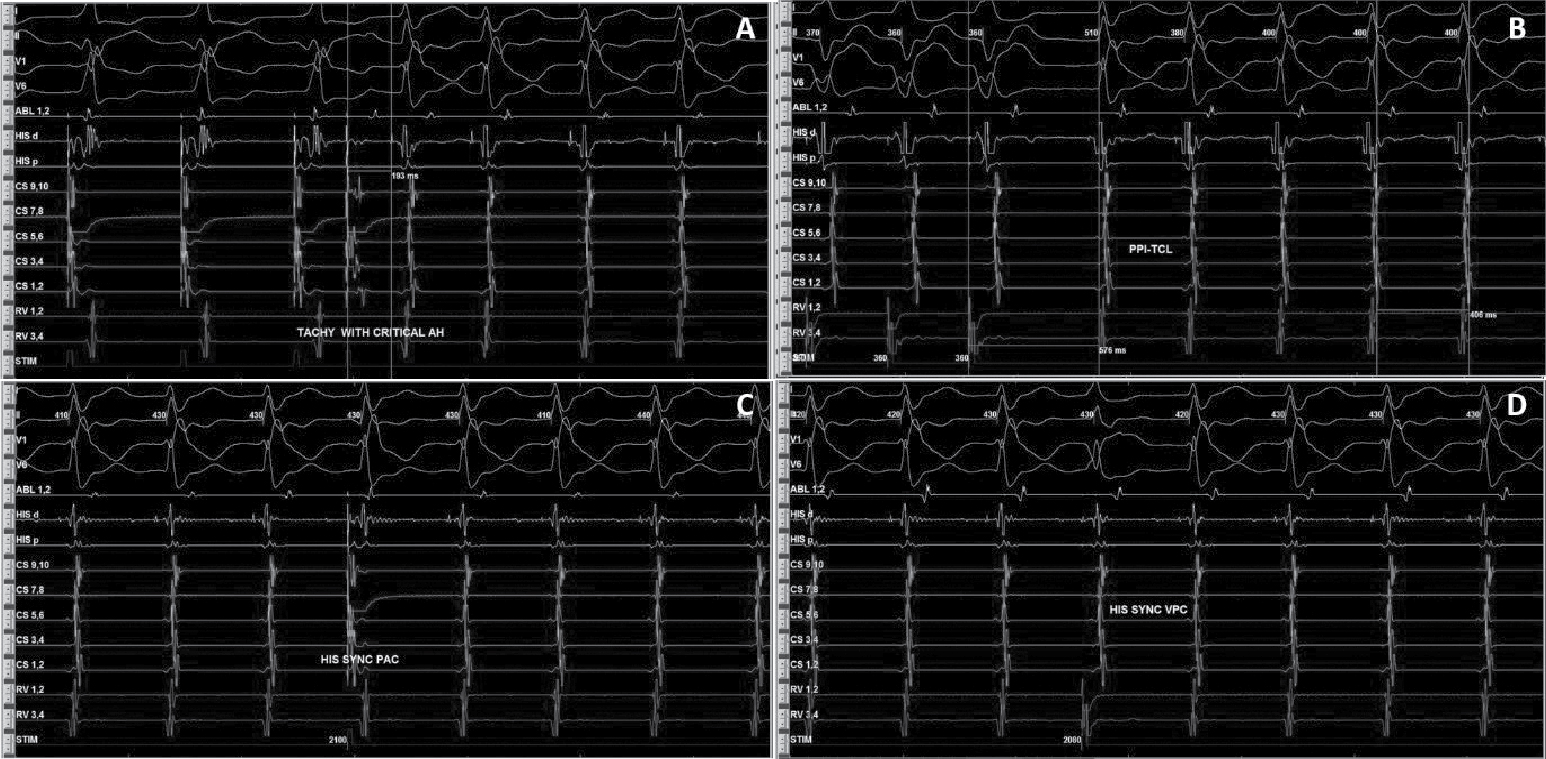

After written informed consent, patient was taken for electrophysiological study. Two quadripolar diagnostic catheters were advanced under fluoroscopy to His bundle region and right ventricular apex. One decapolar catheter was advanced into the coronary sinus. During the electrophysiological study at baseline, atrial-His bundle (AH) and His-ventricular (HV) intervals were 85 ms and 3 ms in sinus rhythm, respectively. There were no atrioventricular (AV) conduction abnormalities. A narrow complex tachycardia (tachycardia cycle length [TCL] = 400 ms) was easily induced during catheter placement with following features: initiation of the tachycardia with a critical AH interval, fixed 1:1 ventriculoatrial (VA) conduction, concentric retrograde activation with VA interval of 37 ms, a post-pacing interval (PPI, 576 ms)–TCL (406 ms) >115 (170 ms) and ventricular overdrive pacing resulted in a VAHV response. His synchronized and early premature ventricular contraction (PVC) did not reset the tachycardia. His synchronized premature atrial contraction (PAC) also failed to reset the tachycardia. The tachycardia was reproducible and consistent (Fig. 2). After confirming the diagnosis of typical AV nodal re-entrant tachycardia (AVNRT) a decision was taken for slow pathway ablation. Using a steerable ablation catheter, with the help of intracardiac electrograms (EGMs) and using fluoroscopy, the region of the slow pathway was identified. Radiofrequency applications were made in the region of the slow pathway while constantly monitoring temperature, impedance, ECG and intracardiac EGMs, monitoring for fast junctional conduction and radiofrequency energy was halted if there was evidence of VA block. Radiofrequency ablation resulted in a junctional rhythm with intact AV conduction, which is a typical response. The AV nodal slow pathway was successfully modified (Fig. 3).

Figure 2. Intracardiac EGMs showing tachycardia induction with AH jump (A), RV overdrive pacing (B), and response of His synchronous PVCs (C) and PACs (D) diagnostic of typical slow-fast AVNRT.